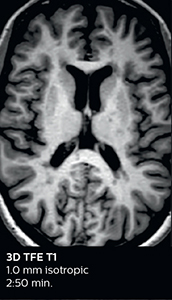

Ingenia Elition 3.0T with Compressed SENSE

3D FLAIR 1.0 x 1.0 x 1.0 mm* 2:50 min.

3D TSE T1w 1.0 x 1.0 x 1.0 mm* 2:10 min.

3D T2w Drive 0.7 x 0.7 x 0.7 mm* 2:52 min.

3D T1w THRIVE 0.7 x 0.7 x 0.8 mm* 1:30 min.

*true voxel size, without interpolation